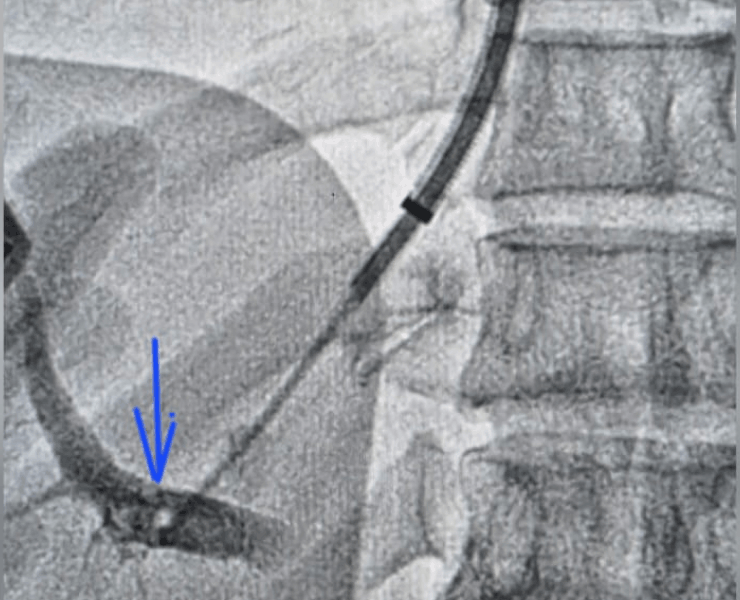

TIPS and DIPS are performed in a specialised catheterisation lab under ultrasound and fluoroscopy (X‑ray) guidance, usually through a vein in the neck (internal jugular vein).

- Transjugular access: a thin catheter is passed from the neck vein into the hepatic or IVC system.

- Portal vein puncture: the right portal vein branch is carefully punctured from inside the liver.

Before and after procedure, we did DIPS procedure on this patient